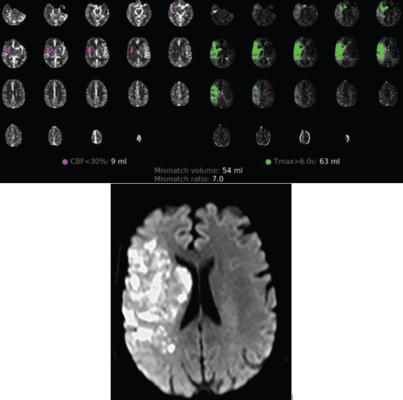

54-year-old patient with COVID-19 who underwent full angiographic reperfusion (extended thrombolysis in cerebral ischemia score = 3) after acute ischemic stroke. Top: Automated readout summary of CT perfusion data at presentation shows large mismatch volume (54 mL). Bottom: Follow-up MR image shows progression in infarction growth, with final infarction volume of approximately 72 cm3 (600% increase from CT perfusion imaging estimate of 9 mL shown in A).

May 17, 2023 — According to an accepted manuscript published in ARRS’ own American Journal of Roentgenology (AJR), SARS-CoV-2 infection may promote continued infarction progression, despite angiographic reperfusion, in vaccine-naïve patients with large-vessel occlusion acute ischemic stroke (AIS).

Ultimately, in this case-control study of vaccine-naïve patients with and without COVID-19 with infarct growth after endovascular reperfusion during acute ischemic stroke, COVID-19 was a significant predictor for absolute infarct growth of 15 cm3 or more (OR, 5.1 [95% CI, 1.0–25.95]; p = .05).

“These findings support the potentially aggressive clinical course of cerebrovascular events in patients with COVID-19, suggesting greater infarction growth and ongoing consumption of at-risk tissues, even following angiographic reperfusion,” Dehkharghani et al. added.